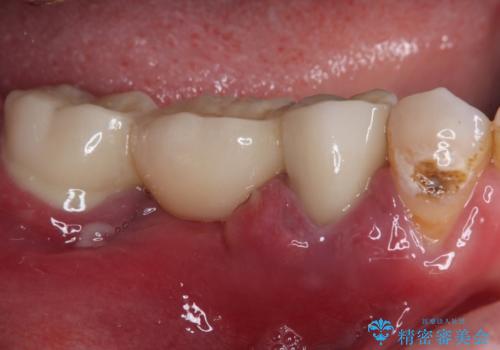

痛みが続いているとのことで、むし歯が神経組織に及んでいる可能性があるため、処置を行うに当たりラバーダムによる唾液の排除を行うこととしました。

手前の歯はむし歯の範囲が広いためオールセラミッククラウンにて、最後方歯は部分的なむし歯であったのでPGAインレー(プラチナゴールドインレー)にて治療を進めることとしました。